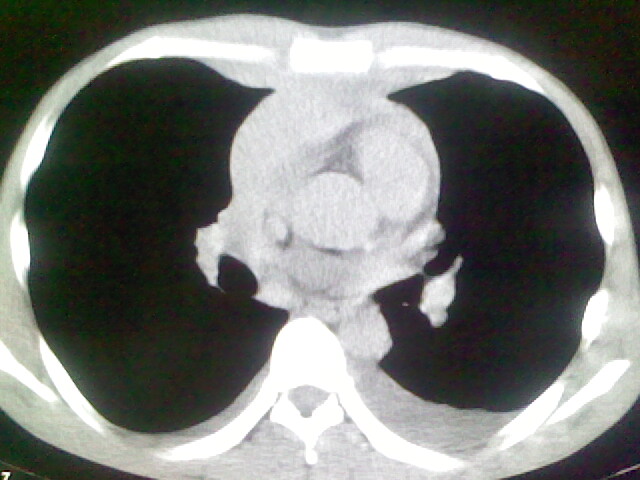

以下是引用杀毒软件在2008-9-3 6:11:00的发言:[br]侵袭性胸腺瘤------一般不侵到气管旁[br][br]考虑----纵隔淋巴瘤,心包及胸膜受累

以下是引用wzr在2008-9-3 5:30:00的发言:[br]侵袭性胸腺瘤

以下是引用随光逐影在2008-9-3 7:07:00的发言:[br]1)考虑淋巴瘤可能。2)双侧胸腔积液(以左侧为甚)。3)心包积液。